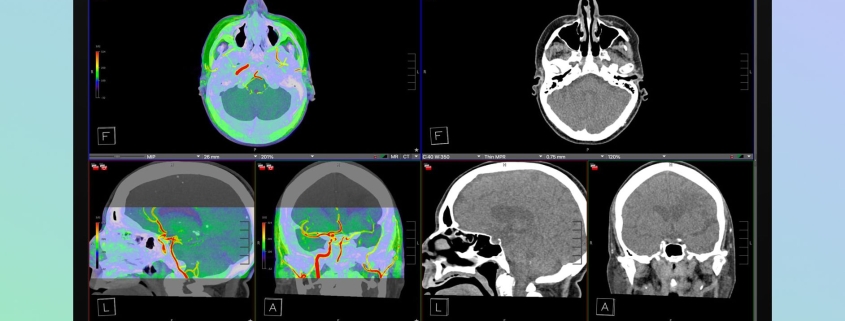

In a move that’s sending shockwaves through both the tech and medical communities, Apple has unveiled its latest innovation: the Studio Display XDR. This isn’t just another high-end monitor—it’s a revolutionary tool that’s poised to transform how radiologists and medical professionals work, potentially replacing expensive single-purpose medical imaging displays with a versatile, Apple-designed solution.

At first glance, you might think this is just Apple’s answer to professional monitors like those from Dell or LG. But look closer, and you’ll discover something extraordinary: built-in DICOM medical imaging presets and a dedicated Medical Imaging Calibrator. For those unfamiliar with medical terminology, DICOM (Digital Imaging and Communications in Medicine) is the international standard for handling, storing, printing, and transmitting medical imaging information. It’s the backbone of modern radiology.

What makes this so groundbreaking? Traditionally, radiologists have relied on specialized, often prohibitively expensive medical imaging monitors that cost thousands—sometimes tens of thousands—of dollars. These displays are purpose-built for one task: viewing medical images with the precision and accuracy required for diagnosis. Now, Apple is essentially saying, “Why buy a specialized tool when you can have a multipurpose powerhouse that does it all?”

Let’s dive into what makes the Studio Display XDR so special. Apple has packed this display with cutting-edge technology that rivals—and in some cases surpasses—dedicated medical imaging monitors:

• Mini-LED backlight with 2,304 local dimming zones for unparalleled contrast and brightness control

• 2000 nits of peak HDR brightness, ensuring even the darkest details in medical scans are visible

• 1,000,000:1 contrast ratio for true-to-life image reproduction

• 120Hz refresh rate for smooth, flicker-free viewing during long diagnostic sessions

• Advanced color accuracy that meets medical imaging standards

But here’s where it gets really interesting: the display includes a dedicated mode switching option that lets users seamlessly transition from standard viewing modes to radiology-specific viewing modes. This means radiologists can quickly adapt the display to their specific needs without compromising on quality or accuracy.